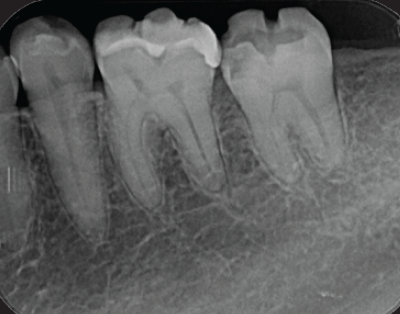

右下6番カリエスが進行し、遠心根根尖部周囲に透過像を認める(図9)。歯髄生活反応(―)

(図9)右下6番はカリエスが進行し、歯髄壊疽から遠心根根尖部に透過像を認める

歯髄腔は狭窄し近心根は複雑な湾曲を呈する